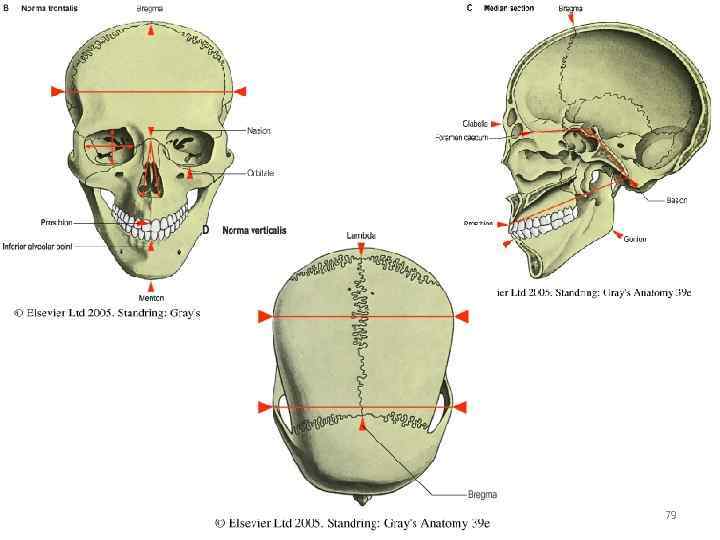

Анатомические изображения срединной сагиттальной линии черепа